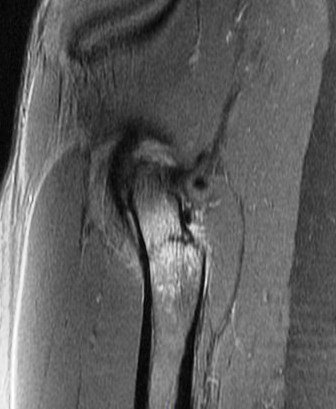

Figure 2 for case Calcar stress fracture ( RID4695 )

Figure 2